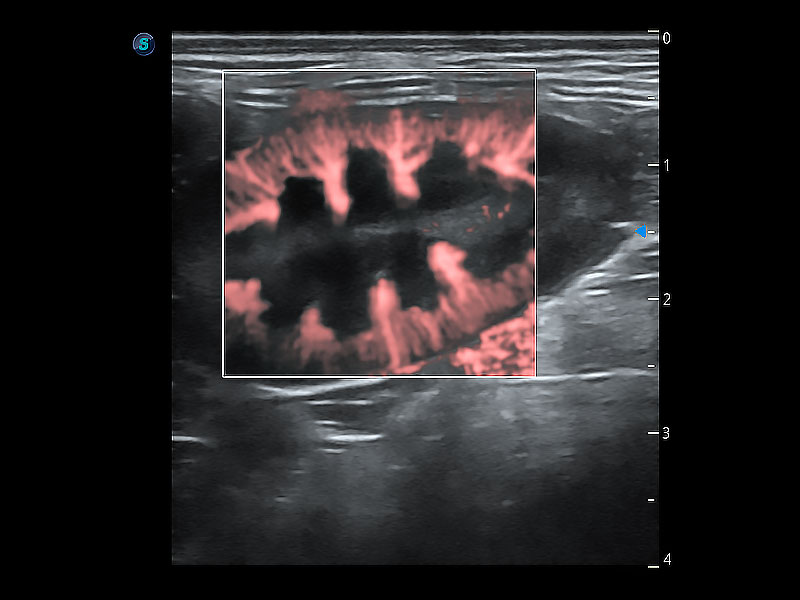

• Micro F 显微血流成像

极大提升超低速微细血流的检出能力,同时更精准地滤除软组织和超声信号,为兽用医生提供以往无法通过常规血流获得的疾病诊断信息。

优异的基础图像

ProPet 80 全新的动物超声智能软件和丰富的探头群,为动物医生提供了高清晰度和精细分辨率的图像,无论在宠物、马科、畜牧还是实验室动物等应用中都可以轻松应对,为您的日常工作带来满意的体验。

(犬)肾脏显微血流